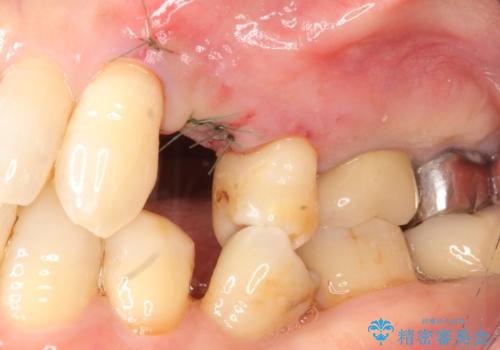

精査したところ、歯が割れており保存不可能な状態であったためやむなく抜歯しました。

患者様のご希望によりインプラント治療を行いました。

インプラントの種類:スプライン ツイスト

被せ物の種類:メタルボンドクラウン

固定様式:スクリュー固定